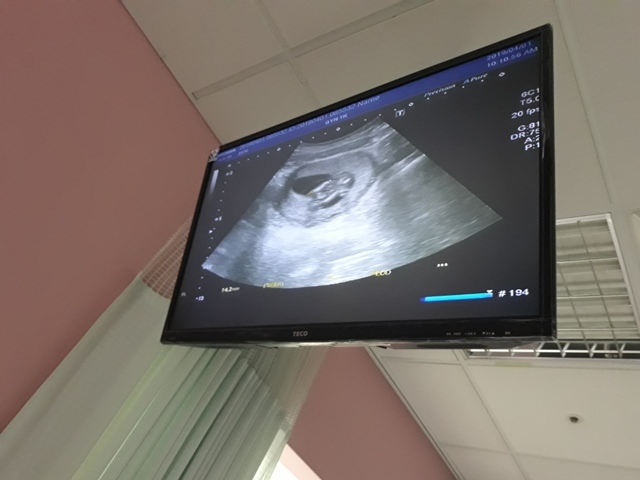

當小純進入診間看診時,我並沒有進去,因為小純說,有時男生不能進去,會被請出來。在外頭等待的我感到很緊張,不久之後,謢理人員請我進入診間,我嚇了一跳,想說發生什麼事了,進入之後,得知小純真的懷孕了,而且已懷了九星期又五天。看診的醫師說,驗孕棒第二條線淡淡的,沒想到胚胎照出來那麼大了,說Baby很健康。還說一閃一閃的是他的心跳,有頭、有手、有腳還有臍帶。小純後來說看了內心覺得很感動,才叫我一起進去看。

小純肚子裡的Baby超音波圖↓